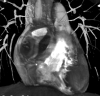

A previously healthy 32-year-old female hailing from Mexico presented to the emergency department with rectorrhagia. Caseating granulomas were detected on histopathological analysis from cecum ulcerative lesions. A purified protein derivative skin test resulted positive. In order to exclude pulmonary tubercolosis, a CT lung scan was performed: a rounded and voluminous mass, located above the right atrioventricular cardiac junction, was unexpectedly revealed. Further, a cardiac magnetic resonance and a coronary angiography disclosed a giant (5 × 4,8 cm) isolated aneurysm of proximal right coronary artery with severe thrombotic layering. The patient was treated with isoniazid, rifampin, ethambutol, and pyrazinamide; after approximately 2 months of treatment, she had complete resolution of cecal lesions. Anticoagulant oral therapy with warfarin was started and the patient was submitted to coronary artery grafting bypass surgery.